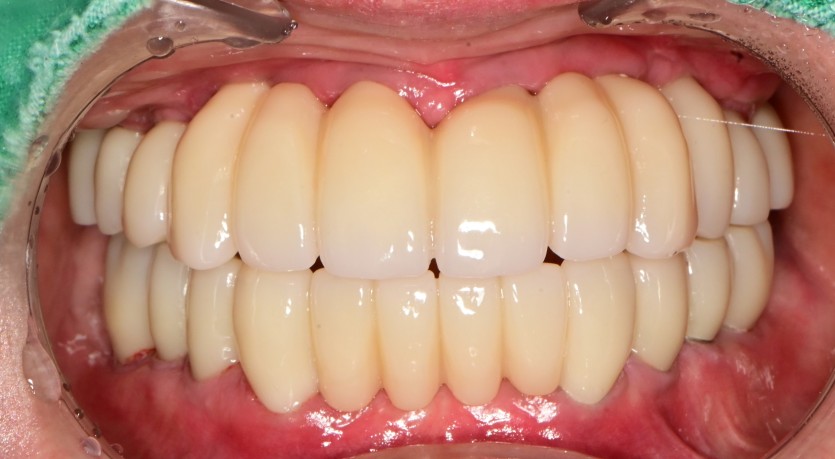

만 45세 전체 임플란트 증례

전체 임플란트 증례입니다.

18개의 임플란트로 완성하였습니다.